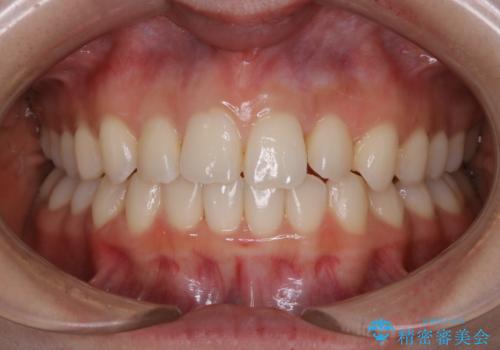

動きづらい前歯のねじれもマウスピース(インビザライン)で改善

- 前から2番目の歯が捻じれていることが気になるとご相談にいらした方です。

インビザラインFULLで治療を行いました。

上の前から2番目の歯は、一般的に周囲の歯と比べて小さく、動きづらい歯であると言われています。前歯にゴムかけを行うことで理想的な位置まで歯を動かしてくることが出来ました。